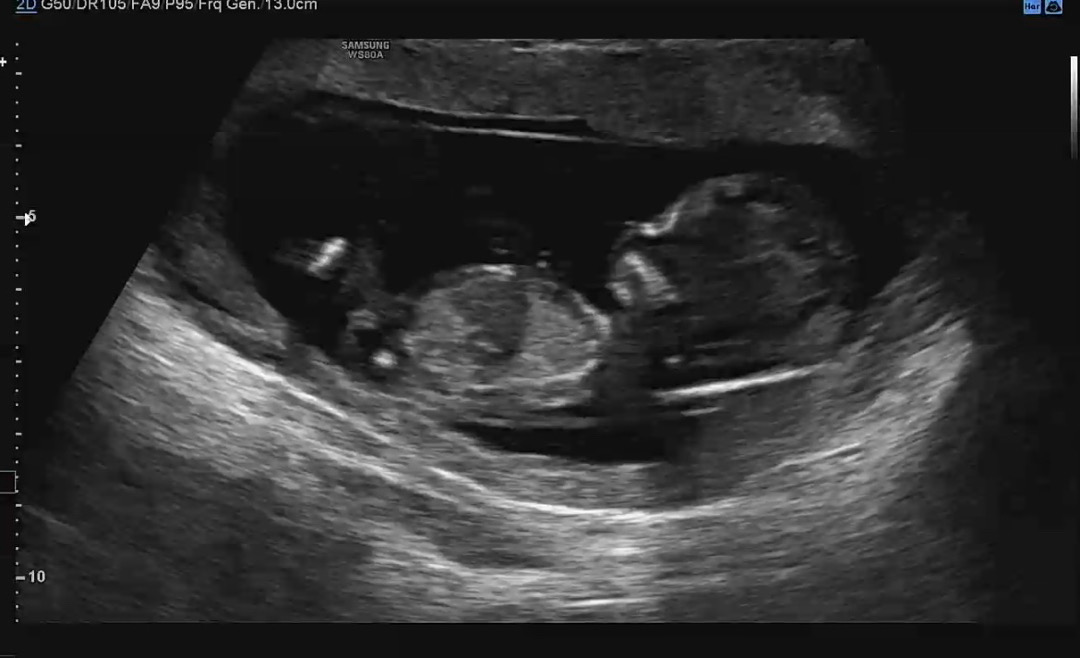

13주차 각도법 봐주세요 !!!

혹시 각도법으로 아들인지 딸인지 봐주실수있나욤 ㅎㅎㅎ 저는 봐도 잘 모르겠네여 ㅠ

이사진으론 잘안보여요ㅠㅠ

잘안보이는데 왠지 딸같아요!